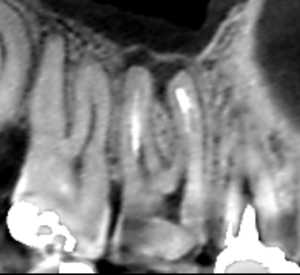

上顎第一大臼歯の頬側根の矢状断のCT画像です。

頬側にある近心根と遠心根の両方に膿の影がみられます。